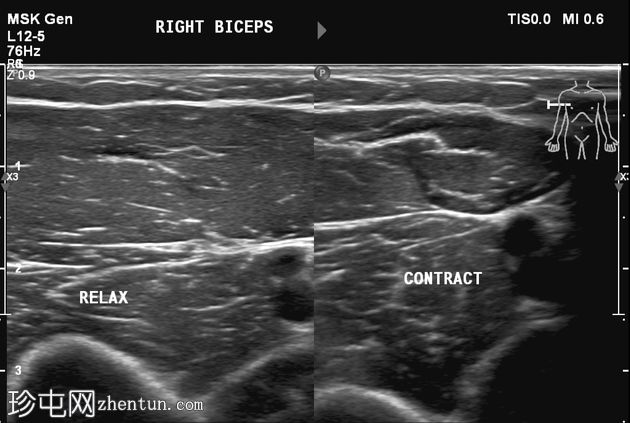

肘关节屈曲及肌肉收缩动态成像:肱二头肌短头和长头肌纤维之间出现充满液体的裂隙,提示局部肌筋膜分离/拉伤。未见肌纤维全层撕裂。肱二头肌远端止点正常。

诊断:肱二头肌短头和长头之间的动态肌筋膜损伤,收缩时裂隙内积液。

静息状态下的图像可能显示正常,这凸显了对有症状患​​者进行动态检查的重要性。